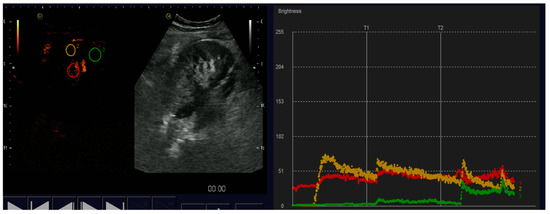

4.1.3. Acute Cortical Necrosis